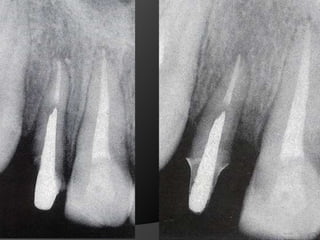

Diagnóstico y Planificación MultidisciplinariaEl examen clínico y la historia clínica nos darán información sobre los factores locales y sistémicos que pueden tener gran influencia en la obtención de un pronóstico para el tratamiento propuesto

Diagnóstico y Planificación MultidisciplinariaHistoria ClínicaAnamnesisFotografía clínica Montaje modelos de estudioEncerados DiagnósticosEvaluación Radiográfica Radiografías PeriapicalesRadiografía PanorámicaEvaluación DentalEvaluación PeriodontalEvaluación EndodónticaEvaluación OclusalEvaluación Articular?